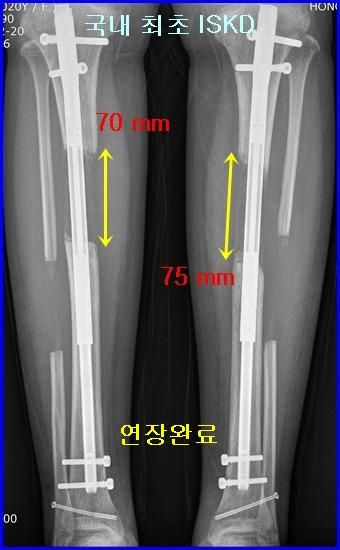

종아리 뼈(경골) 연장 - 국내최초 ISKD